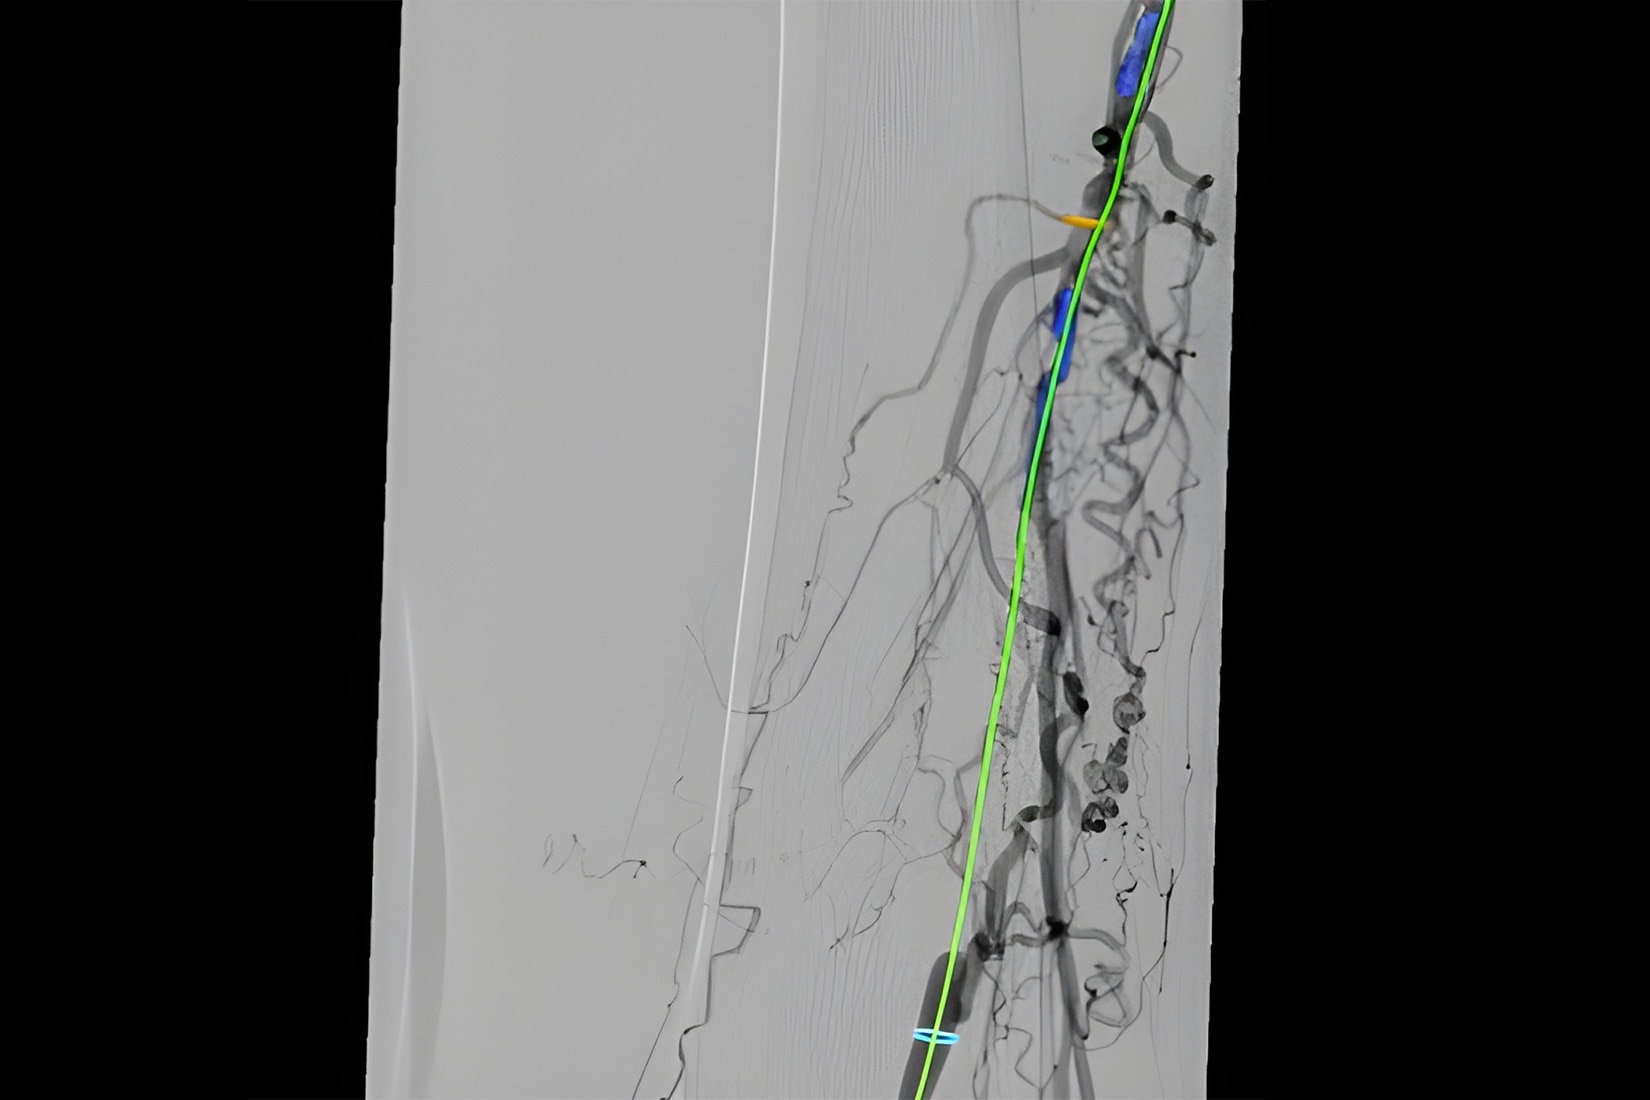

Vessel assist for peripheral

Vessel ASSIST delivers accurate and easy anatomy segmentation and accurate vessel quantification from 3D volumes. It also offers advanced 3D roadmap and augmented image guidance capabilities to guide catheter with confidence.

Guide

Select from the sub-volumes of vessels, centerlines, calcifications and landmarks to overlay on live fluoroscopy for 3D fusion guidance, with digital zoom, to guide recanalization.

Access

Use DSA images on larger Field Of View to image the entire anatomy of interest.